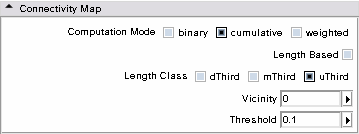

- Connectivity Map panel: